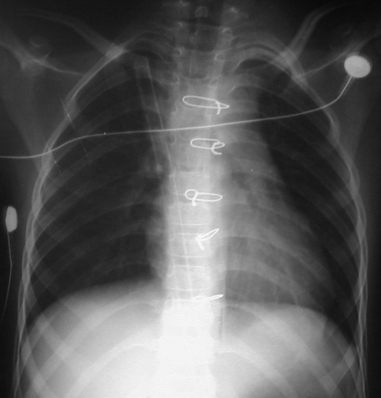

Radiografía del tórax

Radiologia PA Pre-operatoria

Rx. Torax PA. Radiotransparencia conservada en ambos campos pulmonares, sin infiltrados parenquimatosos, hileo y patrón de flujo pulmonar normal, senos costo y cardio-diafragmaticos libres, silueta cardio-mediastinica en posicion y morfologia normal aunque puede notarse el boton aortico borroso, mal definido; El esqueleto y partes blandas sin alteraciones.

Rx Torax AP. Post operatorio 24 horas, unidad de Terapia Intensiva Pediatrica, paciente extubado, electrodos de monitoreo cardiaco, tubo drenaje toracico a trampa de agua, mediastinal, insinuado en cavidad pleural derecha, esteriorizado sub sifoideo, 5 anillos de sutura de alambre de acero de osteosintesis esternal, imagenes pulmonares de aspecto normal, espandidos, sin colecciones costo-cardiodiafragmatica, imagen o silueta cardiomediastinal de aspecto normal.

Rx Post-operatoria